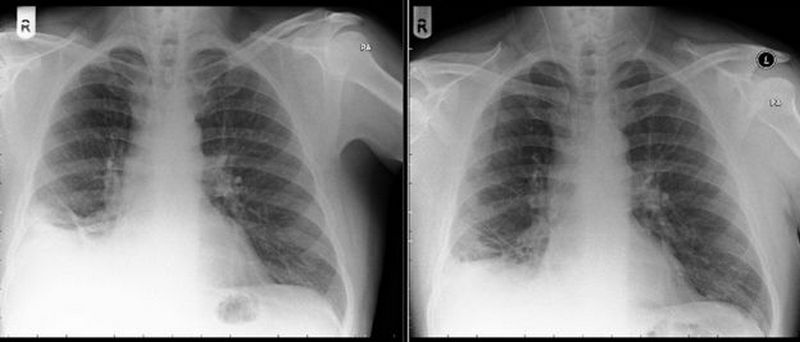

По рентгеновскому снимку невозможно было определить природу новообразования в легких пациента, но оно было видно достаточно ясно. Медики решили провести операцию.

В ходе операции выяснилось, что смертоносная опухоль – это игрушечный дорожный конус, который мужчина случайно вдохнул в 7-летнем возрасте.